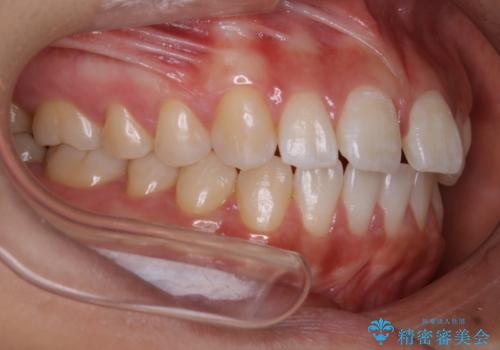

インビザライン矯正 前歯のすきっ歯を治したい

- 上顎の前歯のすきっ歯を治したいとのことで来院されました。

前歯の隙間を閉じる矯正治療の場合、インビザライン適用症例のためインビザラインによる治療をご提案しました。

上唇と歯ぐきを結ぶひも(上唇小帯)が長いと、前歯に隙間が空いてしまうことがあります。今回は隙間を確実に閉じる目的、また矯正後に再び隙間が空かないように、上唇小帯の切除も行っています。